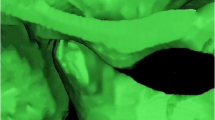

The superior limit of the condyle was determined where the first radiopaque point appeared in the joint space (Fig. 1A, B); The inferior limit of condyle was determined when the sigmoid notch which is between the mandibular condyle and the coronoid process disappeared (Fig. 1C, D). After determination of the conture of interest (VOI), an appropriate greyscale cut-off value was manually selected by scrolling the coronal slices of the condyle so that the condyle contour was visualized. Using this greyscale cut-off value, the contour of VOI was enhanced automatically (Fig. 2A). Then, made a fine adjustments manually by shading or erasing the under-contoured and over-contoured voxels using the function of EditMask. (Fig. 2B) [18]. After the isolation, three-dimensional reconstructions were performed for each condyle using a Mimics tool of calculating 3D from a mask (Fig. 3A, B). The height, superficial area, and volume were measured on the 3-D models, as has been described in previous studies [14, 19].

To investigate the surface remodeling of the condylar head, pre-treatment and post-treatment segmented images were superimposed using both point registration and global registration techniques, employing the least root mean square method [20].

Condylar head height(H1) increased significantly post-treatment (P < 0.05, Table 1). BMD showed a significant decrease in the maximum axil section, the maximum sagittal section, 3D condyle and condylar head (P < 0.01, Table 2). Evaluation of volumetric measurements revealed that 3D condyle volume (P < 0.01, Table 3) and condylar head volume decreased significantly post-treatment (P < 0.05, Table 3). No significant difference was found in other measurements (P > 0.05, Tables 1, 4). Superimposed pre-treatment and post-treatment images showed both bone formation and resorption on the surface of condyle (Fig. 4).

For a comprehensive assessment of condylar surface changes, the utilization of 3D reconstructed images and a superimposition method is indispensable. 3D surface images provide a more precise representation of condylar remodeling compared to conventional 2D images. In the current study, the superimposition of pre-treatment and post-treatment 3D reconstructed images revealed that both bone formation and bone resorption had transpired on the condyle’s surface. This suggests an ongoing adaptation process to the altered TMJ environment.